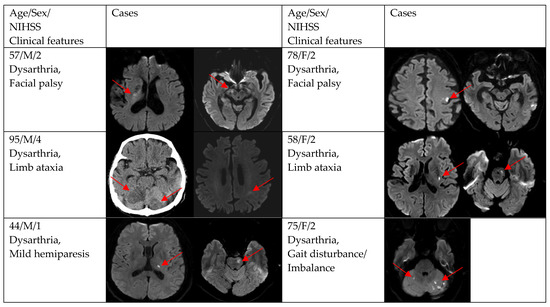

3. Results